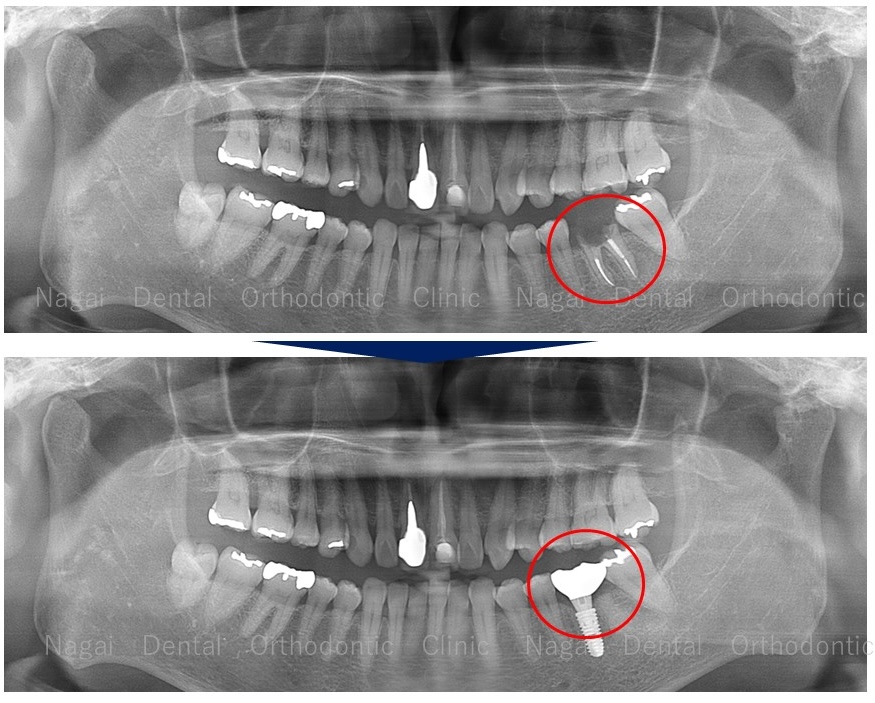

当院のインプラント治療の多くは、抜歯即時インプラント埋入を行います。抜歯したその場でインプラントを埋入する方法です。

従来の歯を抜いて、傷口が治ってからインプランをする方法に比べ期間と回数を短縮し、体への負担も軽くなるからです。

【従来の治療期間・回数】1年~2年・15回~20回

【抜歯即時の治療期間・回数】:4か月~6か月・6回~8回

治療を終えて、数年続いていた不快症状が解消され、両側でバランスよくお食事が出来るようになったと喜んでいただいています。